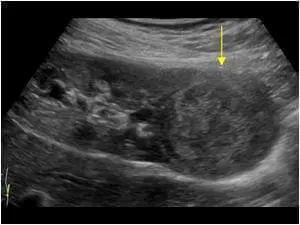

- доброякісні та злоякісні об’ємні утворення бруньок (кісти, абсцеси, ангіоміоліпоми, рак)

- сморшенная, атрофована нирка (прояв хронічної ниркової недостатності, як результат аутоімунних системних захворювань, діабетичної, гіпертонічної нефропатії, і інших патологічних станів, при яких нирки перестають нормально функціонувати)